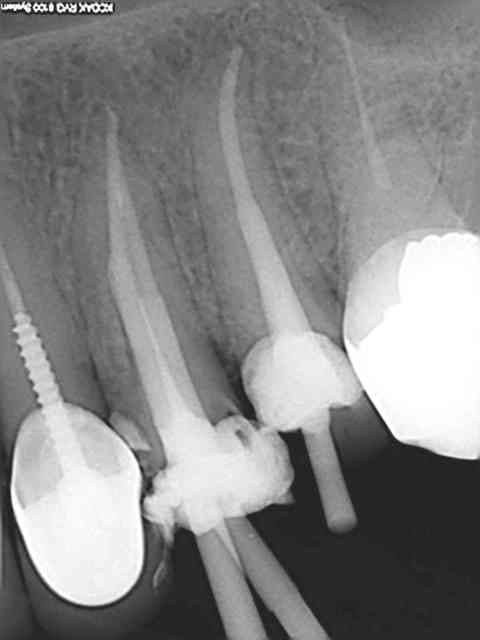

Tu fais comment ton obturation ? Lentulo pâte et monocone ?

Pas de lentulo. Scellement monocone ah+. Effectivement c'est le seul moment ou sur une dent mandibulaire la salive peut faire chier car j'enlève le lingua-fix pour la radio (optragate toujours en place).

D'un autre coté comme le résultat est reproductible il est rare de retirer les cones et de réinstrumenter.